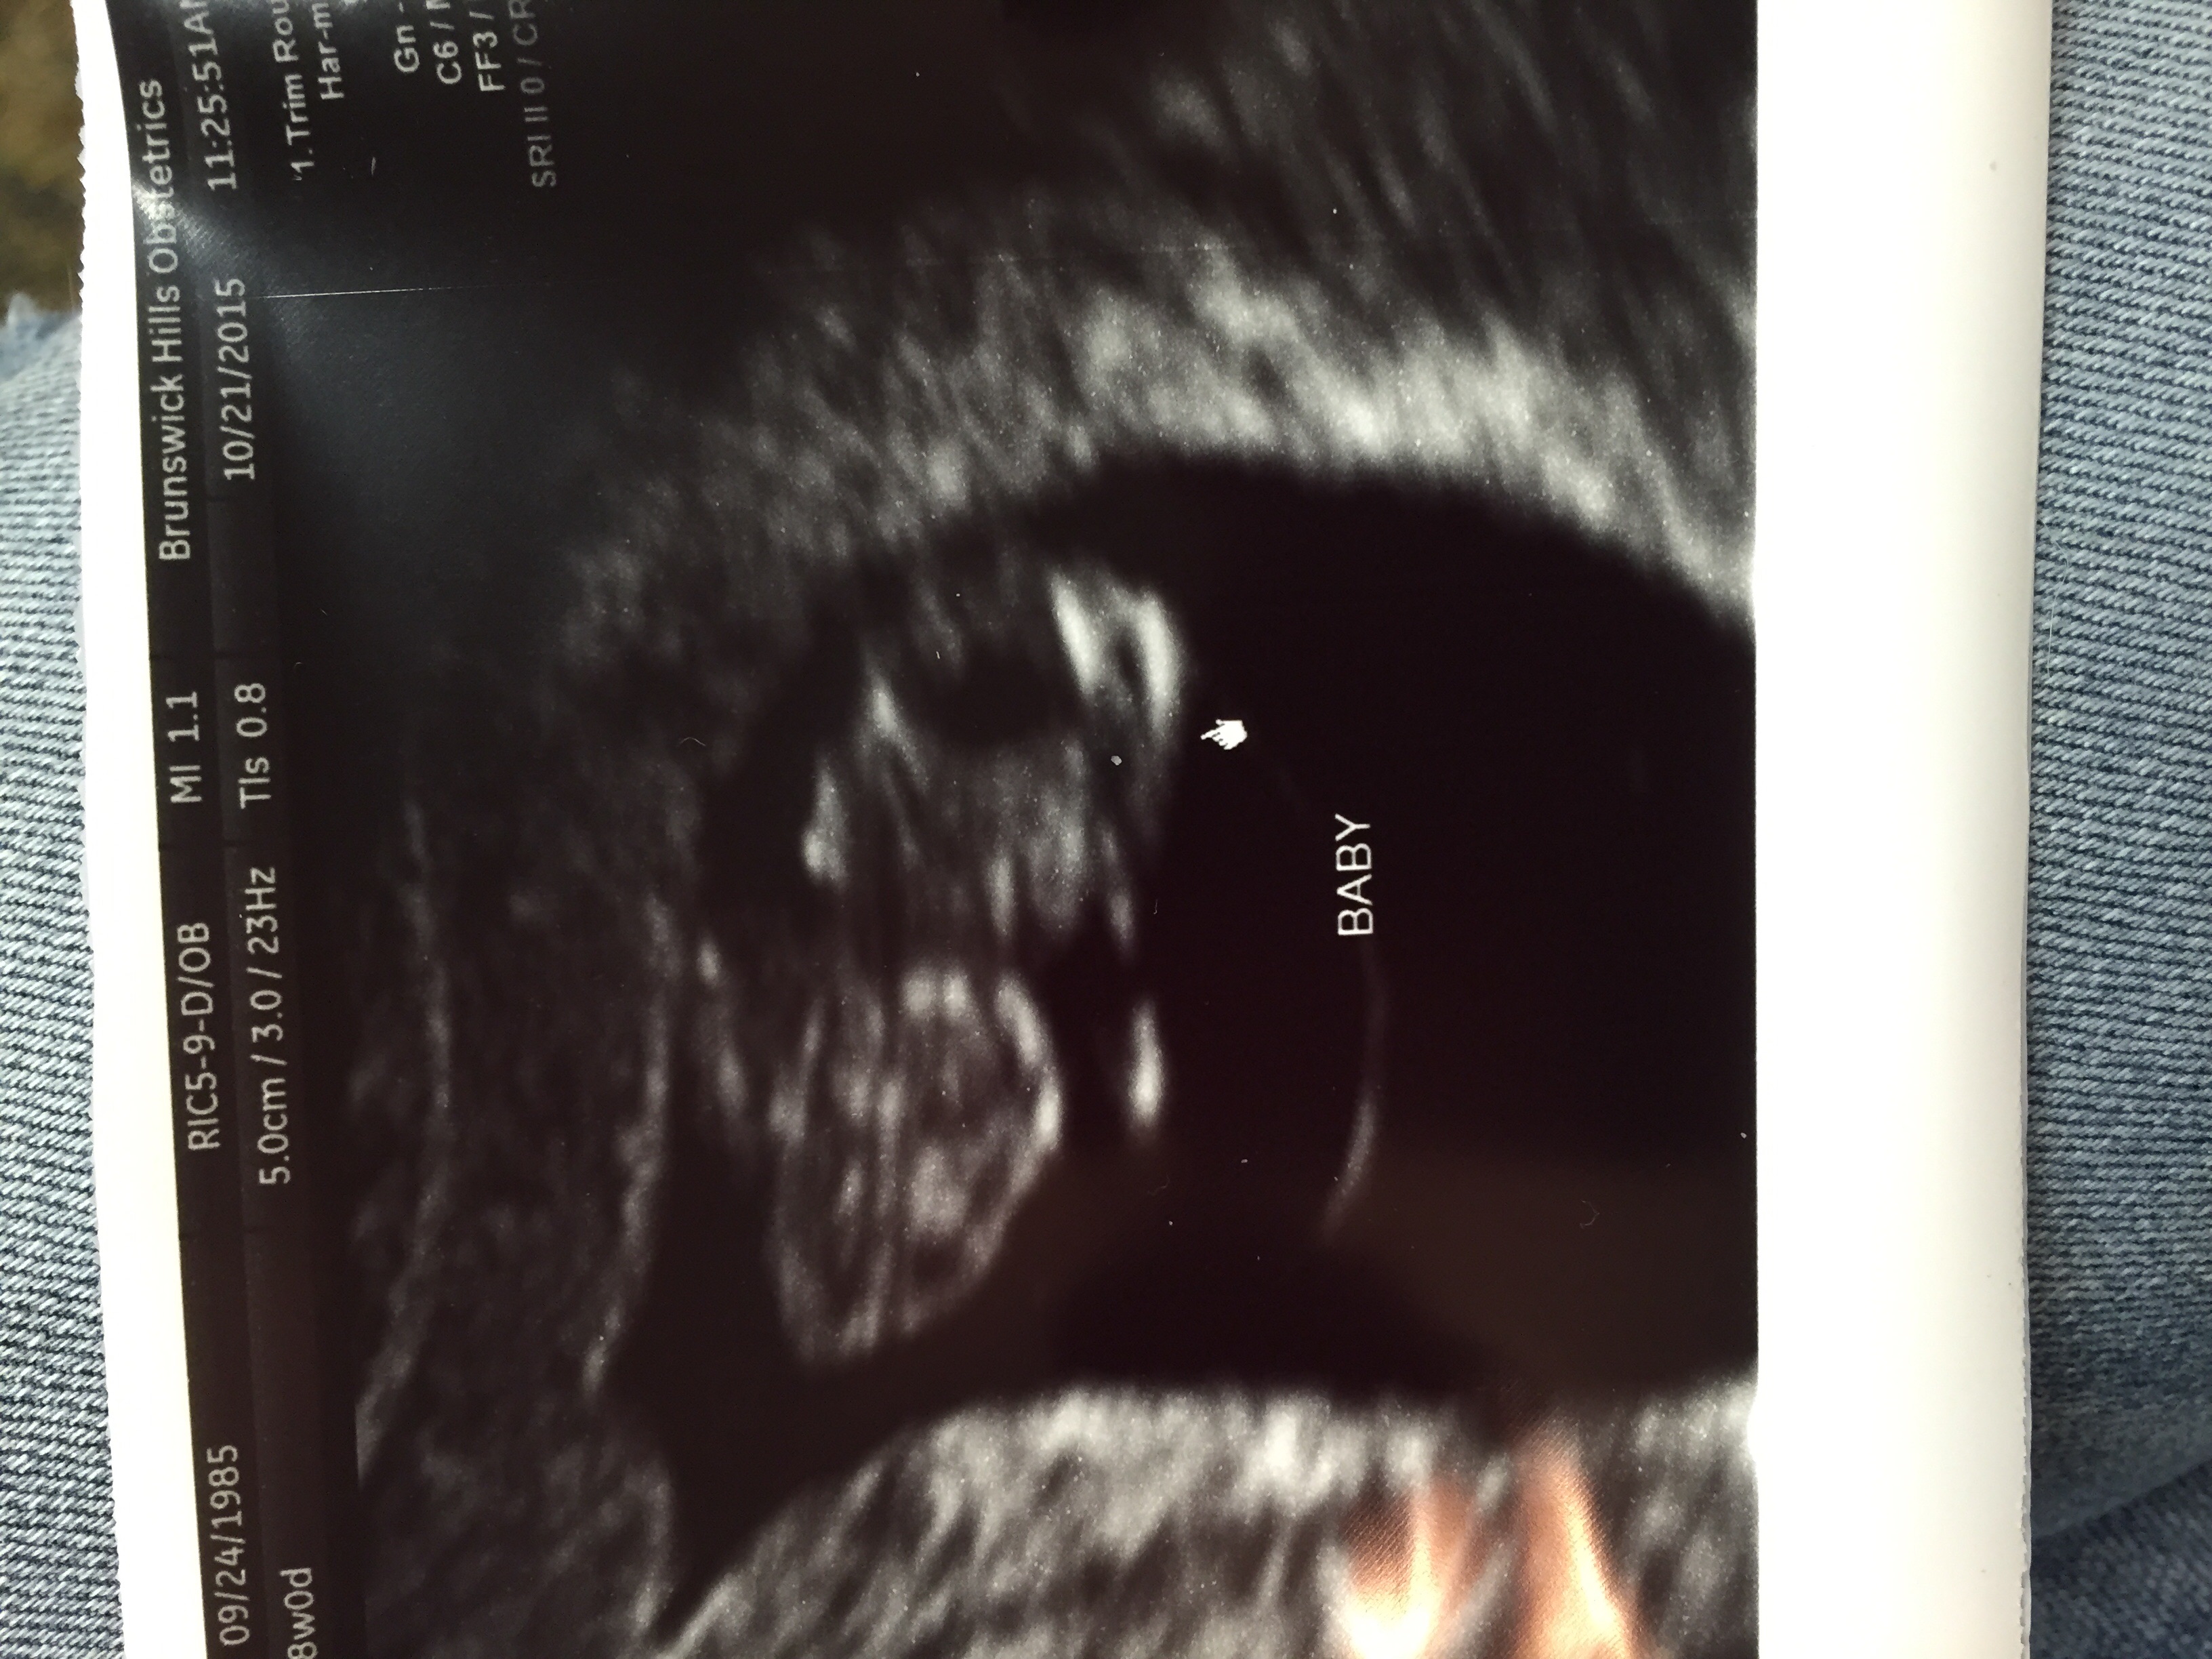

I can't believe this is real!!! Just got done with our first ultrasound awwwww. My little gummy bear with three weird antennas sticking out of his head lol. Due June 6th. I'm 8w3d here. Eek!